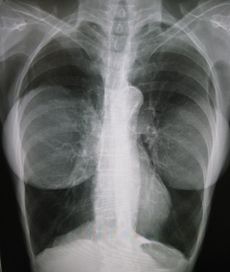

زراعة الثدي، هي جراحة ترقيعية تستخدم لتغيير حجم وشكل أثداء المرأة (معروفة عموماً باسم تكبير الثدي) من أهداف تجميلية إلى إعادة تشكيل الثدي (أي بعد استئصال الثدي أو لتصحيح التشوهات الخلقية بجدار الثدي) أو بوصفها جانباً من جوانب جراحة تغيير الجنس.[1][2][3] موسع أنسجة الثدي هو زرع مؤقت بالثدي يستخدم خلال مراحل اجراءات اعادة بناء الثدي.

وزراعة الثدي هي عادة عملية إدراج كميات من السوائل في الصدر لزيادة حجم الثدي. زراعة الصدر تستعمل كذلك لدى الذكور في العمليات التجميلية والترميمية لجدار الصدر. كما يمكن زيادة حجم الثدي باستخدام جل السيليكون ، أو بغرس أكياس السيليكون المعبئة بالمحلول الملحي ، وفي بعض الحالات من خلال عملية نقل دهون من منطقة أخرى بالجسم [4].